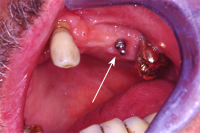

Dieser 67 Jahre alte Patient trägt seit knapp dreissig Jahren im Oberkiefer eine Teilprothese, an die er sich restlos gewöhnt hat und die er eigentlich noch lange behalten möchte (Abb. 7).

Die Situation ist jetzt aber ungünstig geworden, da der alleinstehende Backenzahn auf der einen Seite stark wackelt (Abb. 8, weisser Pfeil). Dieser hat in den 30 Jahren einen viel grösseren parodontalen Schaden erlitten, als die gesamte Gruppe der eigenen Zähne auf der Gegenseite, die keine Parodontitis aufweisen.

Zur Unterstützung haben wir also auf der schwachen Seite ein Implantat mit Sinuslift gesetzt, welches wir viereinhalb Monate später mit einem Druckknopf versehen haben (Abb. 8 und 9). In die Teilprothese wurde als Gegenstück eine Druckknopfhülse eingebaut (Abb. 10).